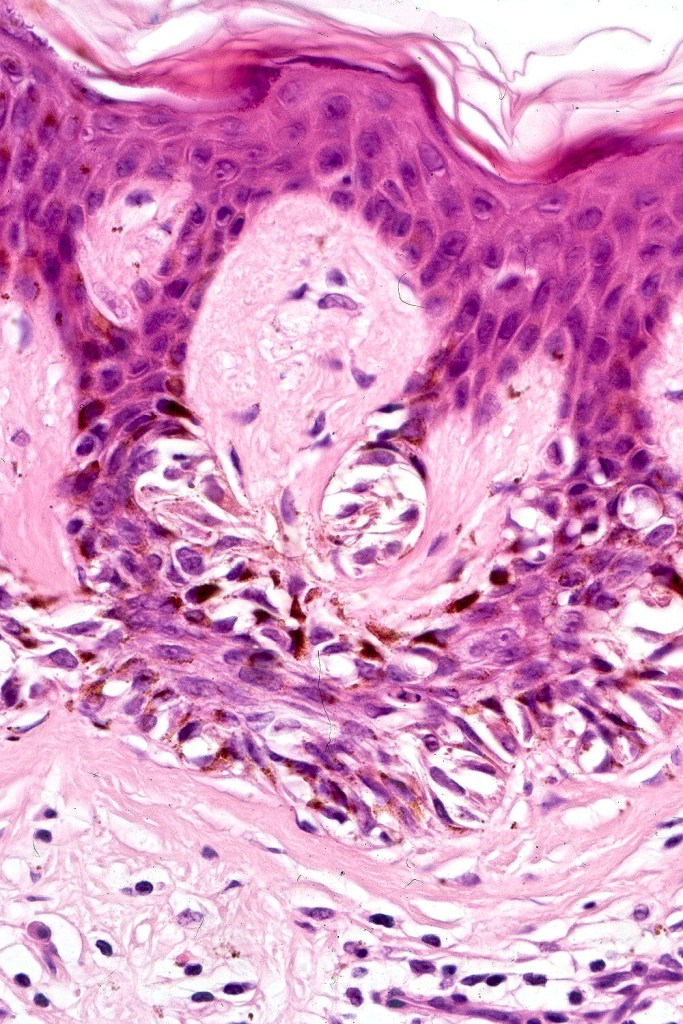

•Architectural disorder- lentiginous and nested, nests abnormally located (at the sides of the rete ridges & overlying the dermal papillae in addition to the tips of the rete ridges rather than solely occupying the tips of the rete ridges as is seen in banal nevi), horizontal orientation & bridging between junctional nests (this should not be confused with bridging between adjacent rete ridge squamous epithelium)

•Host response- eosinophilic & lamellar fibroplasia, increased vascularity, lymphocytic infiltration & pigment incontinence

•In compound lesions, the nest size should be smaller than the junctional ones and the degree of atypia the same or less